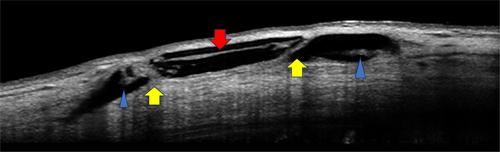

Participants from the FDA phase 1 and 2 trials for the XEN 140 stent were recalled for follow-up examinations between 9 and 12 years after their initial implantation. The stent area was evaluated using anterior segment optical coherence tomography (AS-OCT) in conjunction with clinical assessments. We focused on measuring specific alterations in stent dimensions, such as external surface pitting or ‘nibbling’, complete wall breaches and luminal obstruction.

We evaluated 11 eyes from 9 patients, with an average follow-up period of 11.2 years (SD ± 0.7). The mean preoperative intraocular pressure (IOP) was 22.5 mmHg (SD ± 4.9), which decreased to 14.7 mmHg (SD ± 1.2) a decade after surgery. Notably, four eyes no longer required antiglaucoma medication. Out of the 11 cases, only 8 yielded image quality suitable for analysis, all of which exhibited stent wall nibbling. The average nibbling depth was 70.17 μm (SD ± 36) in the intrascleral area, 79.5 μm (SD ± 18) in the proximal conjunctival region and 42.25 μm (SD ± 5) in the distal conjunctival region. Nibbling was most frequent in the proximal conjunctival area with 26 instances (p = 0.0006), followed by the intrascleral area, 21, and the distal conjunctival section, 9. Hyperreflective lumens were noted in five cases, with one complete stent wall discontinuity.

In cases where imaging provided clear visibility, the stents exhibited signs of morphometric changes after 11 years. This degradation process seems to initiate externally, leading to luminal obstruction and eventual stent failure.